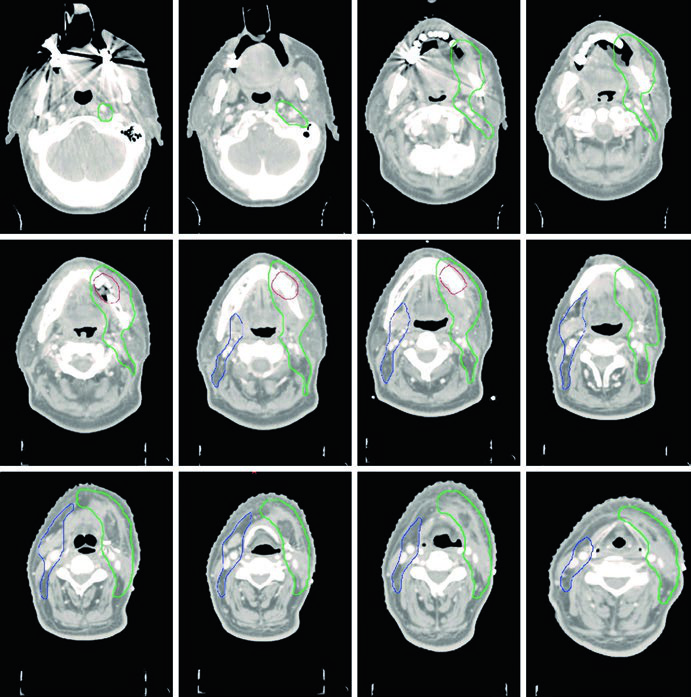

Caso Clínico: Mucosa Jugal T4aN0

A Figura 6.2 mostra um paciente com CEC de mucosa jugal, T4aN0, com invasão cortical óssea mínima, pós-ressecção tumoral com mandibulectomia marginal e esvaziamento cervical esquerdo. Margens amplamente livres. O CTV60 (verde) cobre o leito operatório com níveis I a IV ipsilaterais.

O CTV se estende cranialmente até o sulco vestíbulo-gengival e fossa infratemporal, caudalmente até o sulco vestíbulo-gengival e glândula submandibular, anteriormente até pelo menos a comissura labial, e posteriormente até o trígono retromolar. Bolus é posicionado sobre a pele para garantir dose adequada no CTV de alto risco. A inclusão da parótida ipsilateral deve ser considerada quando há preocupação clínica. Esse padrão de extensão do volume deve ser considerado também nos tumores sinonasais, que compartilham proximidade anatômica.

Caso Clínico: Trígono Retromolar T4aN2b

A Figura 6.3 demonstra um CEC de trígono retromolar, T4aN2b, com envolvimento do pterigoide medial, pós-ressecção com doença residual macroscópica e esvaziamento cervical direito. O CTV70 (vermelho sombreado) é delineado com base nos achados operatórios e nas imagens pré e pós-operatórias.

O CTV59,4 é mostrado em vermelho (região tumoral) e verde (pescoço ipsilateral). O CTV54 (azul) inclui os níveis IB a IV contralaterais.

A fossa pterigopalatina funciona como porta de entrada para disseminação tumoral até a fossa craniana média. Sua cobertura adequada é essencial quando há invasão do músculo pterigoide. Os volumes pós-operatórios devem incluir todo o leito cirúrgico, com visualização da inflamação e edema tecidual na TC de planejamento — achados que delimitam as áreas de manipulação cirúrgica.

Caso Clínico: Gengiva T4aN1 com Invasão Óssea

A Figura 6.4 mostra um CEC de gengiva, T4aN1, com invasão óssea, pós-ressecção tumoral com mandibulectomia marginal e esvaziamento cervical esquerdo. O CTV66 (vermelho) cobre a região de invasão óssea pelo tumor. O CTV60 (verde) inclui todo o leito operatório e os níveis I a IV ipsilaterais.

O CTV54 (azul) abrange os níveis I a IV contralaterais. A decisão de incluir o pescoço contralateral foi baseada na doença nodal positiva (N1) e no estadiamento T4 — ambos fatores que elevam o risco de comprometimento contralateral. Em tumores de gengiva bem lateralizados e com estadiamento mais favorável, essa cobertura poderia ser omitida.

Caso Clínico: Mucosa Jugal T2N3b com Extensão Extranodal

A Figura 6.5 apresenta um CEC de mucosa jugal, T2N3b, pós-ressecção com esvaziamento cervical direito e extensão extranodal no nível IB. Margens negativas, porém próximas na margem profunda. O CTV66 (vermelho) cobre a região nodal com extensão extranodal.

O CTV60 inclui o leito operatório e toda a mucosa jugal, com níveis I a IV ipsilaterais. A extensão do CTV vai cranialmente até o sulco vestíbulo-gengival e fossa infratemporal na altura da borda orbital inferior, caudalmente até o sulco vestíbulo-gengival e glândula submandibular, anteriormente até a comissura labial, e posteriormente até o trígono retromolar. Margens amplas são necessárias mesmo para tumores primários menores. Bolus cutâneo é colocado para cobertura adequada dos CTVs de alto e intermediário risco.

O CTV54 inclui os níveis I a III contralaterais, devido à extensão da doença nodal no pescoço ipsilateral. Esse caso ilustra como a presença de extensão extranodal amplia significativamente os volumes necessários.

Caso Clínico: Assoalho da Boca T4aN2b

A Figura 6.6 demonstra um CEC de assoalho da boca, T4aN2b, com invasão mandibular, pós-hemimandibulectomia direita e esvaziamento cervical bilateral. O CTV66 (vermelho) abrange a área de extensa invasão óssea. O CTV60 (verde) inclui todo o leito operatório e os níveis I a V no lado ipsilateral.

O espaço retroestilóideo ipsilateral é incluído no CTV60 como área de alto risco para metástase nodal, especialmente com comprometimento do nível II. O CTV60 também é estendido para incluir todo o complexo do assoalho da boca. O CTV54 (azul) inclui os níveis I a IV contralaterais.

Este caso demonstra como a invasão mandibular extensa exige delineamento agressivo da região de alto risco, enquanto a doença nodal bilateral justifica cobertura cervical ampla. Na prática, o tratamento do assoalho da boca frequentemente exige técnicas de IMRT com planejamento cuidadoso para limitar dose em mandíbula remanescente, glândulas salivares e via aérea.